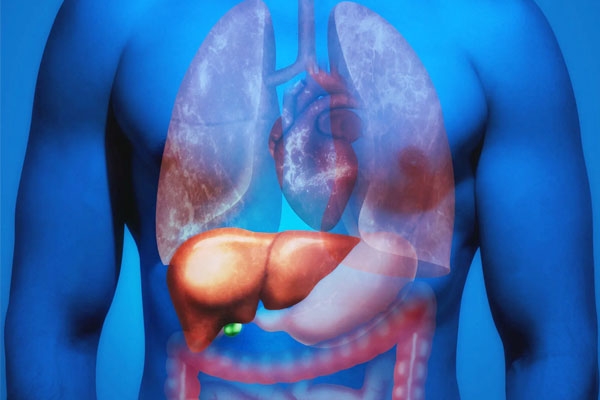

Liver issues, previously associated with older ages, are now becoming common in younger people too. A frequently encountered problem among today’s youth is non-alcoholic fatty liver disease (NAFLD). This condition is on the rise in young adults, largely due to unhealthy lifestyles, bad eating habits, overweight, and obesity. If not addressed promptly, a fatty liver can lead to serious health issues like non-alcoholic steatohepatitis (NASH), liver fibrosis, cirrhosis, or even liver cancer. There’s no need to panic just yet.